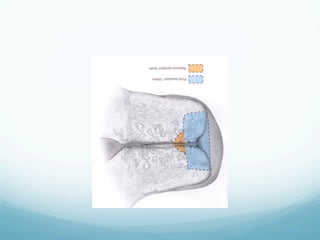

Electrical Loop Excision

—  Should be performed under colposcopic guidance to the

peripheral extent of the abnormal TFZ

—  The patient is grounded

—  Local anesthetic is injected just beneath and lateral to the lesion

—  The cutting current is set at 35-60W

—  The diameter of the loop must be large enough to encompass

the entire lesion

—  A second excision of the endocervical canal using a smaller loop

may be used for high grade lesions

—  Ball coagulation is set at 60W

—  The base is coagulated even if there is no bleeding (non-touch

coagulation)